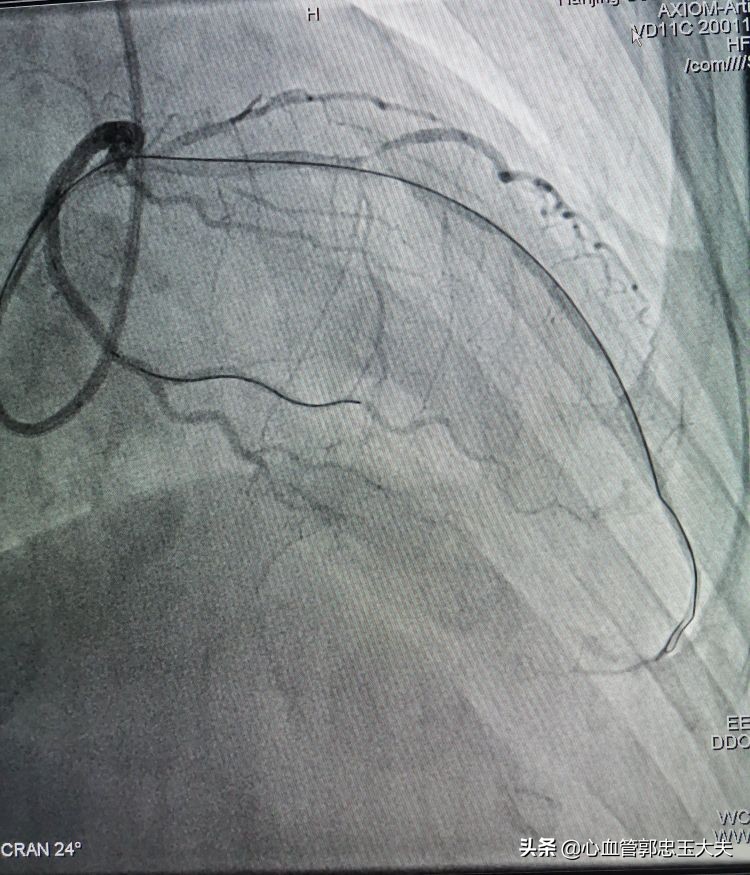

张大爷86岁了,有高血压病史,无烟酒嗜好。因为“反复胸闷头晕数月”入院。冠状动脉CTA示:三支病变,严重钙化合并高度狭窄。行冠脉造影示:前降支中远段钙化,完全闭塞,远端可见血管影。未见明显侧枝循环。(如下图)